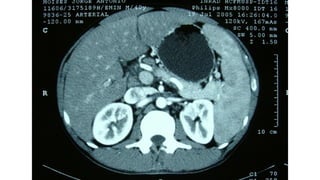

Miliary pattern

Intersticial Randomic micronodular distribution